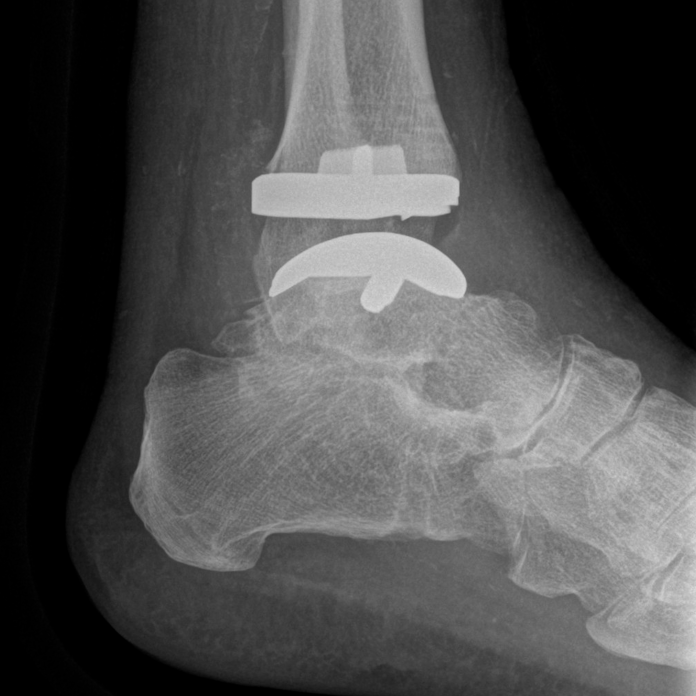

Bei der Sprunggelenk-Endoprothetik hat sich in den letzten Jahren sowohl die Implantat-Qualität als auch die Präzision der Implantation deutlich verbessert. Eine bessere präoperative Planung, bessere Instrumente oder seit neuestem auch Patientenspezifische Instrumente (sogenannte PSI) erlauben es, das Implantat mit einer bisher nicht dagewesenen Genauigkeit einzusetzen. Bei den Patientenspezifischen Instrumenten wird auf Basis von CT-Bildern die OP-Planung im Vorfeld des Eingriffs am Computer durchgeführt (Abb. 1).

Auf Basis der Planung werden dann passgenaue Sägeschablonen produziert, die wie ein Puzzleteil exakt auf den Knochen des Patienten passen und damit die Position des Implantats entsprechend der präoperativen Planung vorgeben (Abb. 2).

Neben der Genauigkeit ist die verkürzte Operationszeit ein weiterer Vorteil des Verfahrens. Die Röntgenbilder nach (Abb. 3 und 4) zeigen eine solche Situation wenige Tage einer Prothesenimplantation am Sprunggelenk.